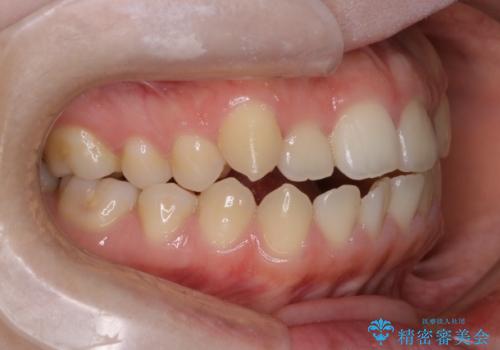

前歯のガタツキ、前歯の噛み合わせ(開咬)をインビザライン治療で治しました

- 前歯のがたつき、噛み合わせが気になるとのことで来院された患者様です。

インビザラインを使用して治療しました。

前歯がしっかり噛んでない状態(開咬)を治すために、前歯にゴムをかける必要があります。ゴムかけは患者様にご協力していただきます。